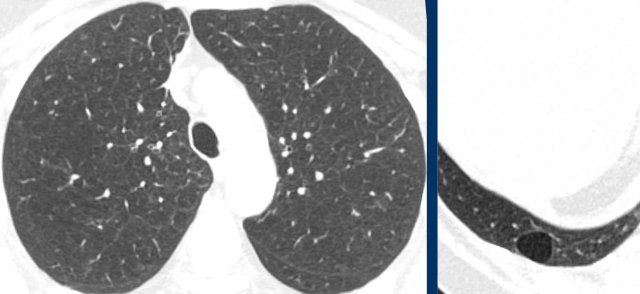

These images are of a 56-year-old woman, who had recurrent pneumothorax and now again presents with a pneumothorax (arrow).

Study the image.

Are these cysts or mimickers?

Is this an incidental finding or do you think it is a cystic lung disease?

What is the most likely diagnosis?

Findings

There are multiple thin-walled cysts - more than four. Notice the localisation near fissures and in the periphery of the lung.

Conclusion

This is a case of Birt-Hogg-Dubé syndrome (BHD).

Discussion

The two cystic lung diseases that frequently present with a pneumothorax, are LAM and BHD.

LAM presents as simple cysts, which are thin walled, round or oval and regularly shaped with a diffuse distribution.

The peripheral and perifissural location of BHD cysts often gives the cysts sharp angles that causes them to have a lenticular shape.

When cysts have this typical appearance, they have an extremely high specificity for the diagnosis of Birt-Hogg-Dubé syndrome.

This is another case of Birt-Hogg-Dubé syndrome.

The cysts are typically located in the periphery of the lung near the mediastinum (black arrow) and close to the fissure (white arrow).